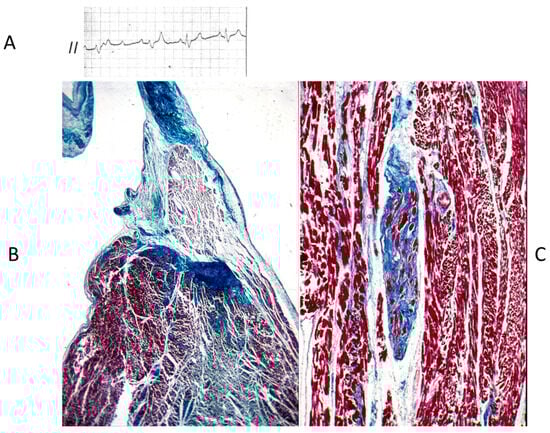

Figure 15.

Histology of Ebstein anomaly with displaced septal leaflet of the tricuspid valve (A) and Kent septal fascicle (B) in a young person who died suddenly [20].

Concerning CHDs of the conduction system in adulthood, ventricular preexcitation (VPE) represents the smallest malformation, consisting of a fascicle of ordinary myocardium (1–2 mm thick) known as the Kent fascicle. It is usually located in the lateral rings (Figure 19A). It connects the atria to the ventricles (Figure 19B) and is bare of the decremental properties of the Tawarian System, which the opposite, as it is located in the central AV septum and consists of specialized conducting tissue endowed with decremental properties.

The Kent fascicle accounts not only for VPE but also for atrial reentry with palpitations by supraventricular tachycardia. In the case of an atrial fibrillation burst (usually about 500 beats per minute), because of the absence of a slowing-down of the electrical impulse, a step one-to-one transmission to the ventricles may trigger a lethal ventricular fibrillation (Figure 20).

Figure 20.

Sudden death in Wolff Parkinson White syndrome: atrial fibrillation turns into ventricular fibrillation.